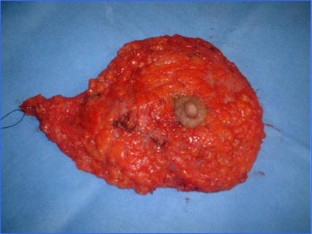

Fig. 2